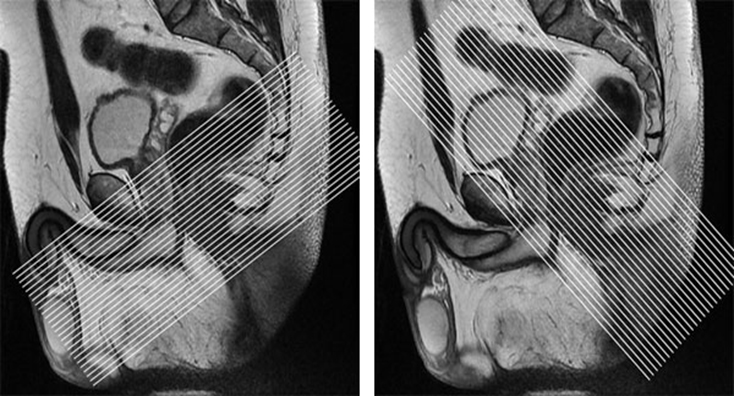

| SAG | T2 | TSE | 2.5mm | 0mm | No | 24mm, fit to patient | Mid-femoral head to mid-femoral head. Freq A-P. Consider using an anterior Sat band if lots of abdominal wall motion. Use to plan oblique planes. |

| AX Oblique | T1 | TSE | 3.5mm | 0.8mm | No | 18-20mm | Freq A-P to avoid bowel motion ghosting into uterus and bladder. Plan slices axial to the anal canal. |

| AX Oblique | T2 | TSE | 3mm | 0.8mm | No | 18-20mm | Freq A-P to avoid bowel motion ghosting into uterus and bladder. Plan slices axial to the anal canal. |

| AX Oblique | T2 | TSE FS | 3mm | 0.8mm | Yes | 18-20mm | Same parameters as AX OBLIQUE T1 TSE. Freq A-P to avoid bowel motion ghosting into uterus and bladder. Plan slices axial to the anal canal. |

| COR Oblique | T2 | TSE FS | 3mm | 0.8mm | Yes | 18-20mm | Freq A-P. Plan slices coronal to the anal canal. |